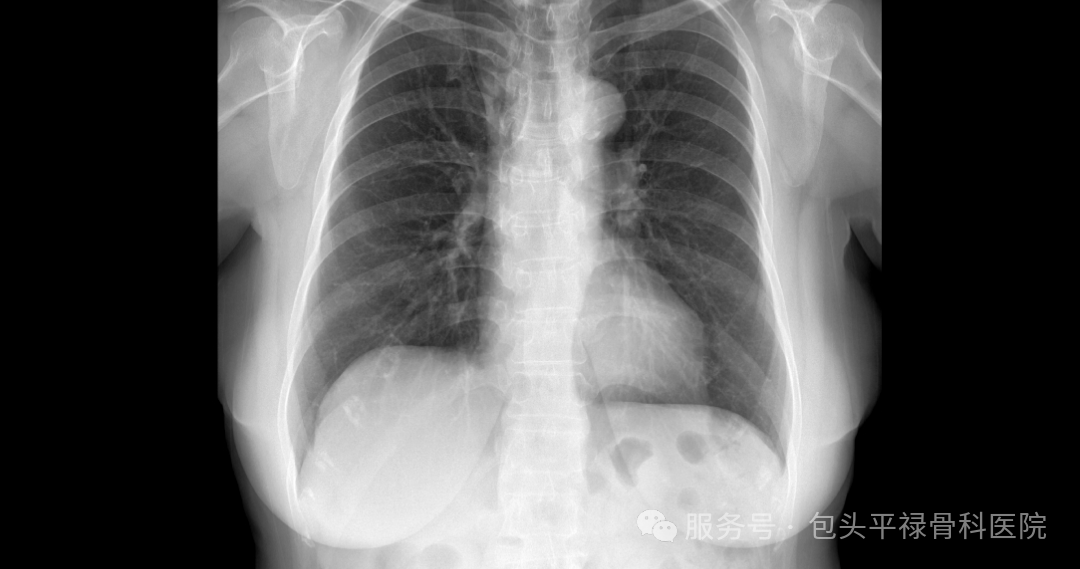

DR-CT-MRI影像对比

图源:包头平禄骨科医院

DR:骨科“侦察兵”,又快又省钱

DR,即数字X射线成像,它利用X射线的穿透能力成像,X线会穿过人体在底片上留下黑白色影像,当它遇到被遮挡的部位(如骨骼)时无法穿透,在底片上显示为白色,反之,则显示为黑色。

胸部:检查肋骨是否骨折,脊柱是否侧弯、骨折;判断肺部是否有炎症、肿瘤、结核、胸腔积液、气胸等情况。